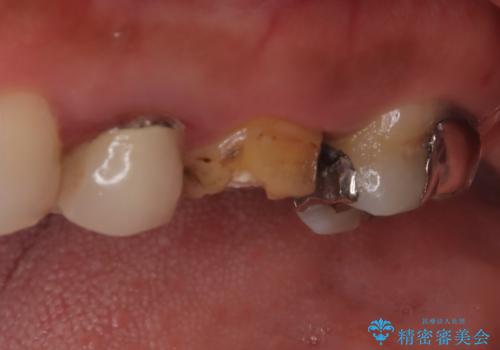

【破折ファイル除去】他院で折れた根管治療の器具をとってほしい

- 他院で折れた根管治療の器具をとってほしいという主訴で来院されました。

マイクロスコープで根管内を観察すると、除去できる状態だったため破折ファイル除去を行いオールセラミッククラウンにて修復治療しております。